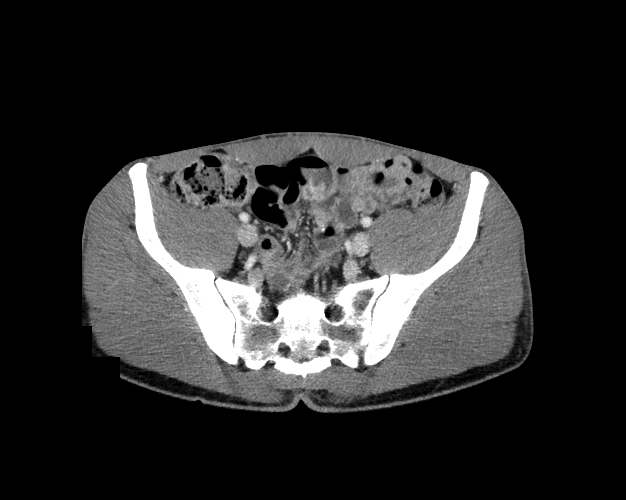

Body

Covers abdominal CT anatomy.